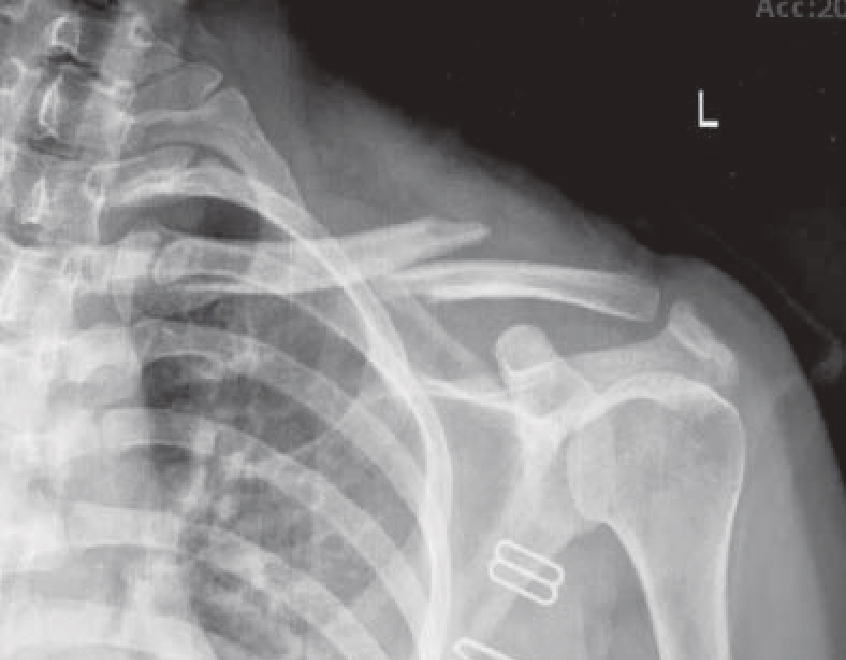

X线检查为锁骨骨折首选的检查方法[10]。最常用的摄影体位为锁骨后前位,拍摄范围应包括锁骨全长、肱骨上1/3、肩胛带及上肺野,必要时需另拍摄胸片。前后位像可显示锁骨骨折的上下移位,45°斜位像可观察骨折的前后移位(图1—2)。CT检查多用于复杂的锁骨骨折,如波及关节面及肩峰的骨折。尤其对于累及关节面的骨折,CT检查优于X线检查。三维重建CT图像可清楚地显示锁骨骨折块的移位情况(图1—3)。

图1—2 锁骨中段骨折X线片